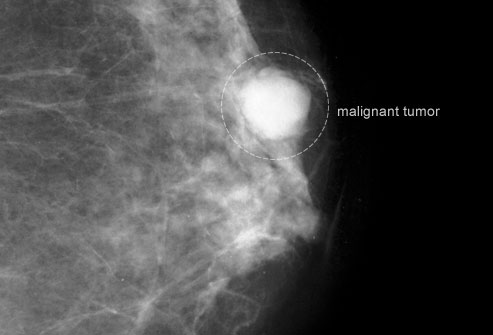

乳腺钼靶筛查

乳腺钼靶是一种低剂量X光射线检查,虽然正常结果不能完全排除癌症可能,但是这种检查能够在你有感觉前发现肿块。当你的年龄处于四十多岁时,你应该每年进行一次乳腺钼靶检查。50至74岁之间时,每两年检查一次。当然,如果你属于高危人群,医生可能见你更频繁地接受检查。